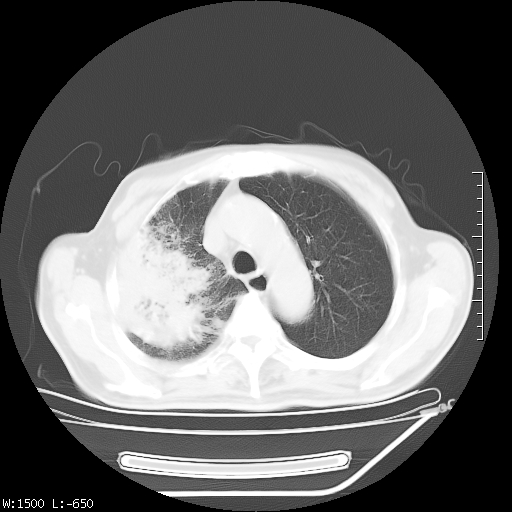

标题: CT23994:男、72、咳嗽、气短两月余,近来消瘦。 [打印本页]

标题: CT23994:男、72、咳嗽、气短两月余,近来消瘦。

tb可能性大(双肺均可见片状密度增高灶,其内可见低密度空洞)。

右上肺大片状密度增高影,与胸膜关系密切,内见低密度透亮影,胸膜下可见三角形不张影,左下肺沿支气管走形结节影,纵膈内淋巴结显示。考虑结核并疤痕性不张可能性大,建议穿刺活检,排除肺泡癌。